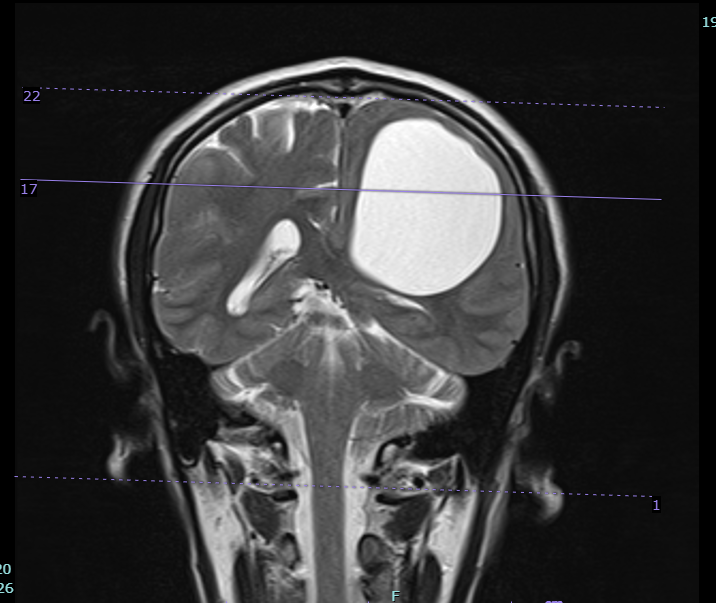

Sau khi tiến hành thăm khám, chụp chiếu, kết hợp với các biểu hiện lâm sàng, người bệnh được hội chẩn và chẩn đoán đa u nang trong não, chưa loại trừ nang sán não. Trong nhu mô não có rất nhiều nang to, nhỏ. Trong đó, nang kén lớn nhất kích thước khoảng 5cm x 7cm, đè ép nhu mô não khiến người bệnh yếu, liệt nửa người.

Ảnh MRI trước mổ của bệnh nhân liệt nửa người: Nang sán lớn nhất nằm trong nhu mô bán cầu não bên trái |